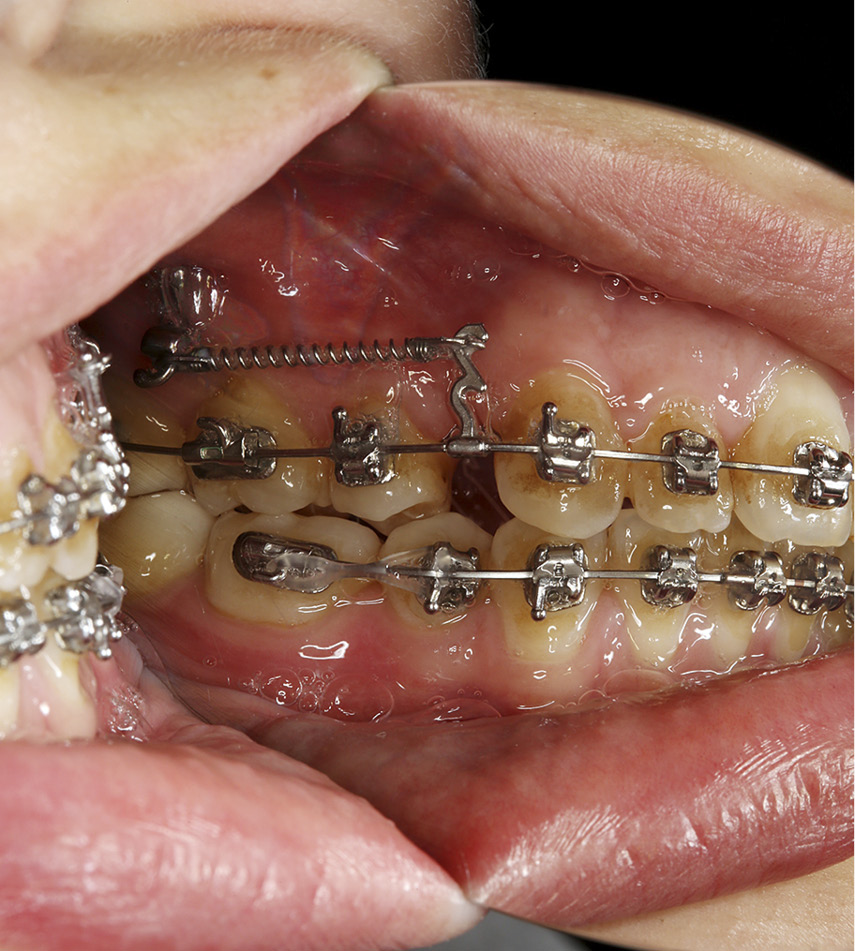

Wykorzystanie zmodyfikowanych minipłytek Bollarda jako tymczasowych szkieletowych zakotwień w leczeniu ortodontycznym

TITLE: Use of modified Bollard miniplates as temporary skeletal anchorage devices in orthodontic treatment

STRESZCZENIE: W celu przeciwdziałania siłom wytwarzanym w czasie przesuwania zębów konieczne jest zastosowanie systemów zakotwień. System minipłytek Bollarda umożliwia osiągnięcie zakotwień maksymalnych w prosty i mało obciążający dla pacjenta sposób. Zestaw składający się z 17 elementów pozwala na prostą implantację i szybkie obciążenie kliniczne. Obok postulowanych początkowo zastosowań pojawiają się coraz to nowe możliwości klinicznego wykorzystania tego rozwiązania. Prosta metoda zabiegu, mała liczba powikłań i pozytywne odczucia pacjenta sugerują, że ta innowacyjna metoda może wkrótce stać się standardowym postępowaniem w określonych przypadkach klinicznych.

SUMMARY: To prevent forces that are generated during orthodontic treatment it is necessary to use anchorage devices. The Bollard miniplates system enables obtaining definitive anchorage points in a relatively simple and patient-friendly way. The complete set contains 17 elements and allows for easy implantation and relatively quick clinical load. Aside from originally postulated applications, new clinical possibilities of this solution are arising. Easy procedure, low complication risk and positive patient feedback may suggest that this innovative method [...]